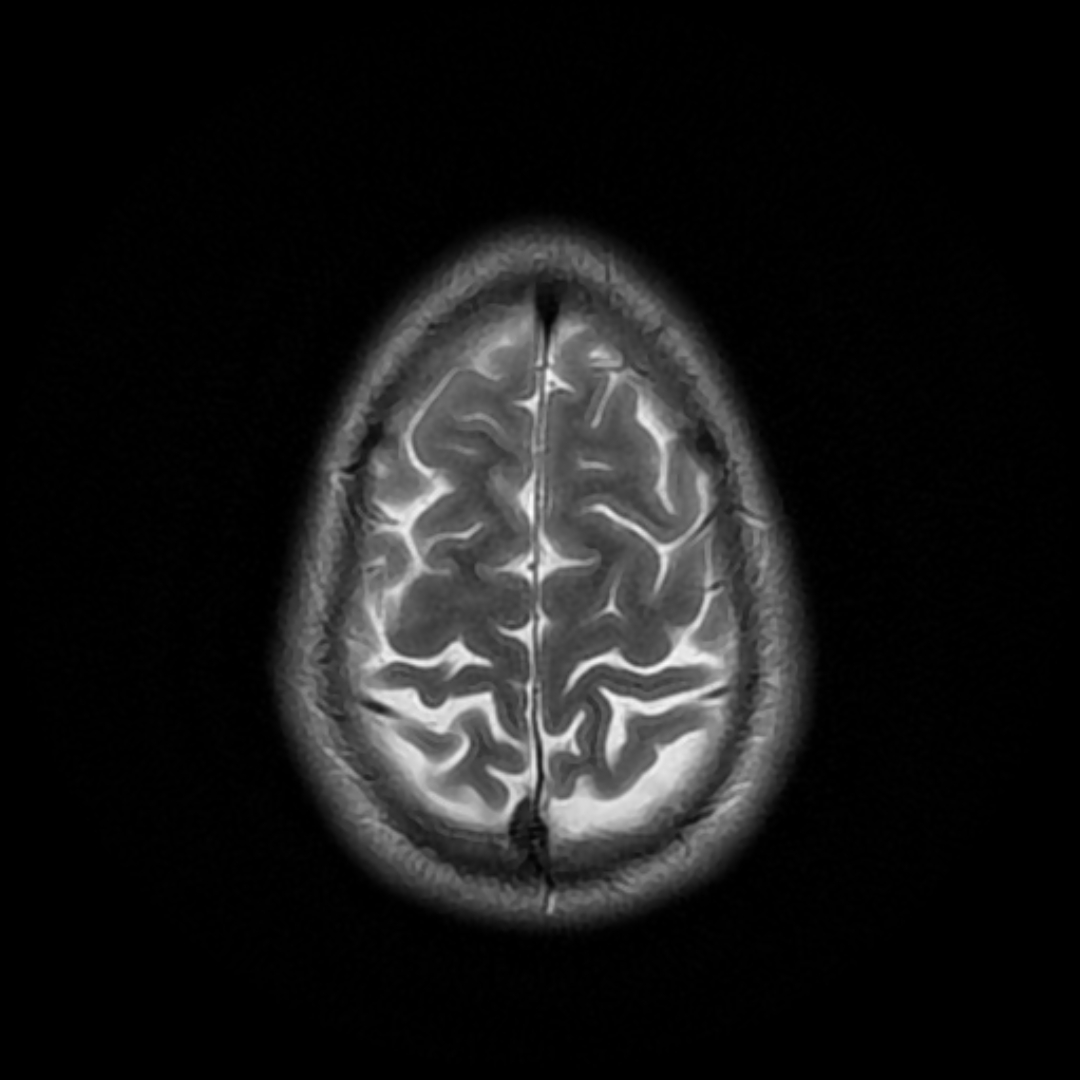

Standard adult head phantom with brain parenchyma, CSF, skull, and ventricles

Brain FDG-PET phantom showing cortical glucose metabolism pattern, useful for Alzheimer's disease and epilepsy evaluation